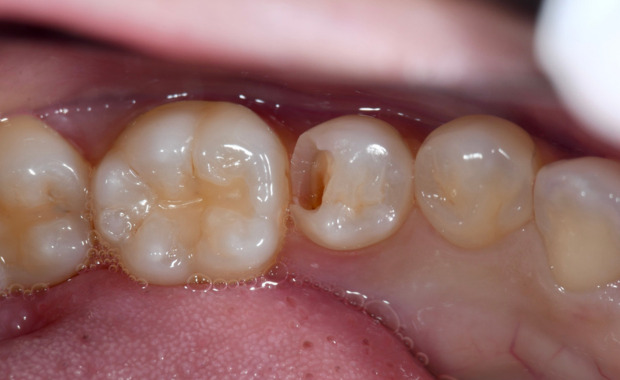

C2 自覚症状を感じ始める

虫歯がまだ神経に達していませんが、痛みや冷たいものなどがしみるなどの症状が現れます。 自然治癒では回復不可能なため、虫歯菌に感染した部分を削り取り、詰め物で修復します。